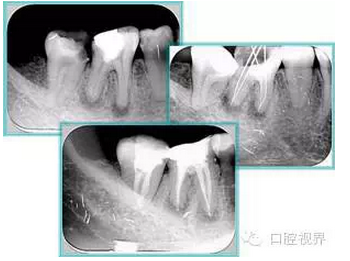

右圖及下圖為器械折斷的 X 線片。箭頭處示折斷器械。

解決方法: ( 1 )取出。 ( 2 )通過(guò)。 ( 3 )重新確定工作長(zhǎng)度,充填。 ( 4 )根尖手術(shù)。

器械折斷可以不用取出,取出的原因多是患者心理因素。留在里面的器械關(guān)鍵是進(jìn)行消毒,預(yù)防性使用抗感染藥物,預(yù)防感染。

右圖箭頭處示臺(tái)階形成。

解決方法: ( 1 )器械預(yù)彎。 ( 2 )若出現(xiàn)銼的螺紋擰緊,立即換用小號(hào)銼。 ( 3 )一旦到達(dá)WL,即按照從小到大順序預(yù)備根管。 ( 4 ) H銼幫助提高切割效率。